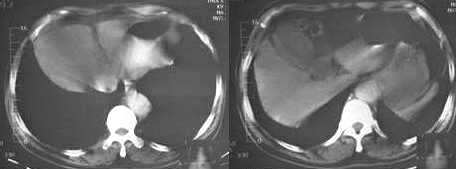

男,60岁,反复头痛,头昏,测血压最高240/120

临床怀疑嗜镉细胞瘤。做ct想了解肾上腺有无肿块。

2.1187 图 是否为胃腔内寄生虫?还是其他呢?

胆囊旁、肝脏前缘为运动伪影。胃内后方考虑肠管,建议此类检查前喝0.7%泛影葡安800ml后再扫描。